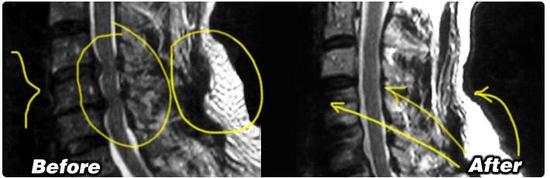

在自然医学期刊中发表的一份研究中,研究人员发表利用干细胞衍生神经元让老鼠受损皮层脊髓束再生的实验已经成功了,促进了一些功能。

在此之前,这些受损的组织都没有成功再生过。

研究人员在实验中使用老鼠和人的神经祖细胞,将这些细胞嫁接到老鼠受损的脊髓部分。他们用化学信号稳定地引导干细胞地形成脊髓组织,生成可以提高前肢运动的功能性突触。